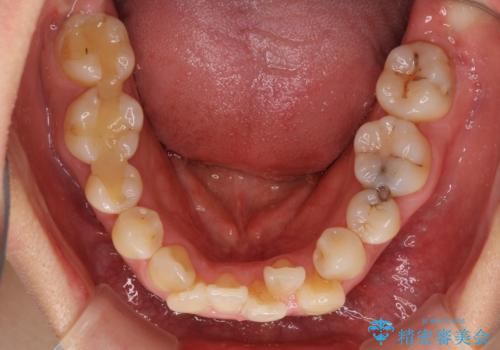

骨格的に上顎は狭く、下顎は右側にシフトしていたため、右側臼歯はクロスバイトとなっていました。

上顎骨を急速拡大装置により拡大し、ワイヤー装置による抜歯矯正治療を行うこととしました。